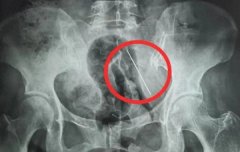

• 老人抱孙子玩腰间4厘米钢针扎进肚

钢针 老人 缝衣针 2026/03/03